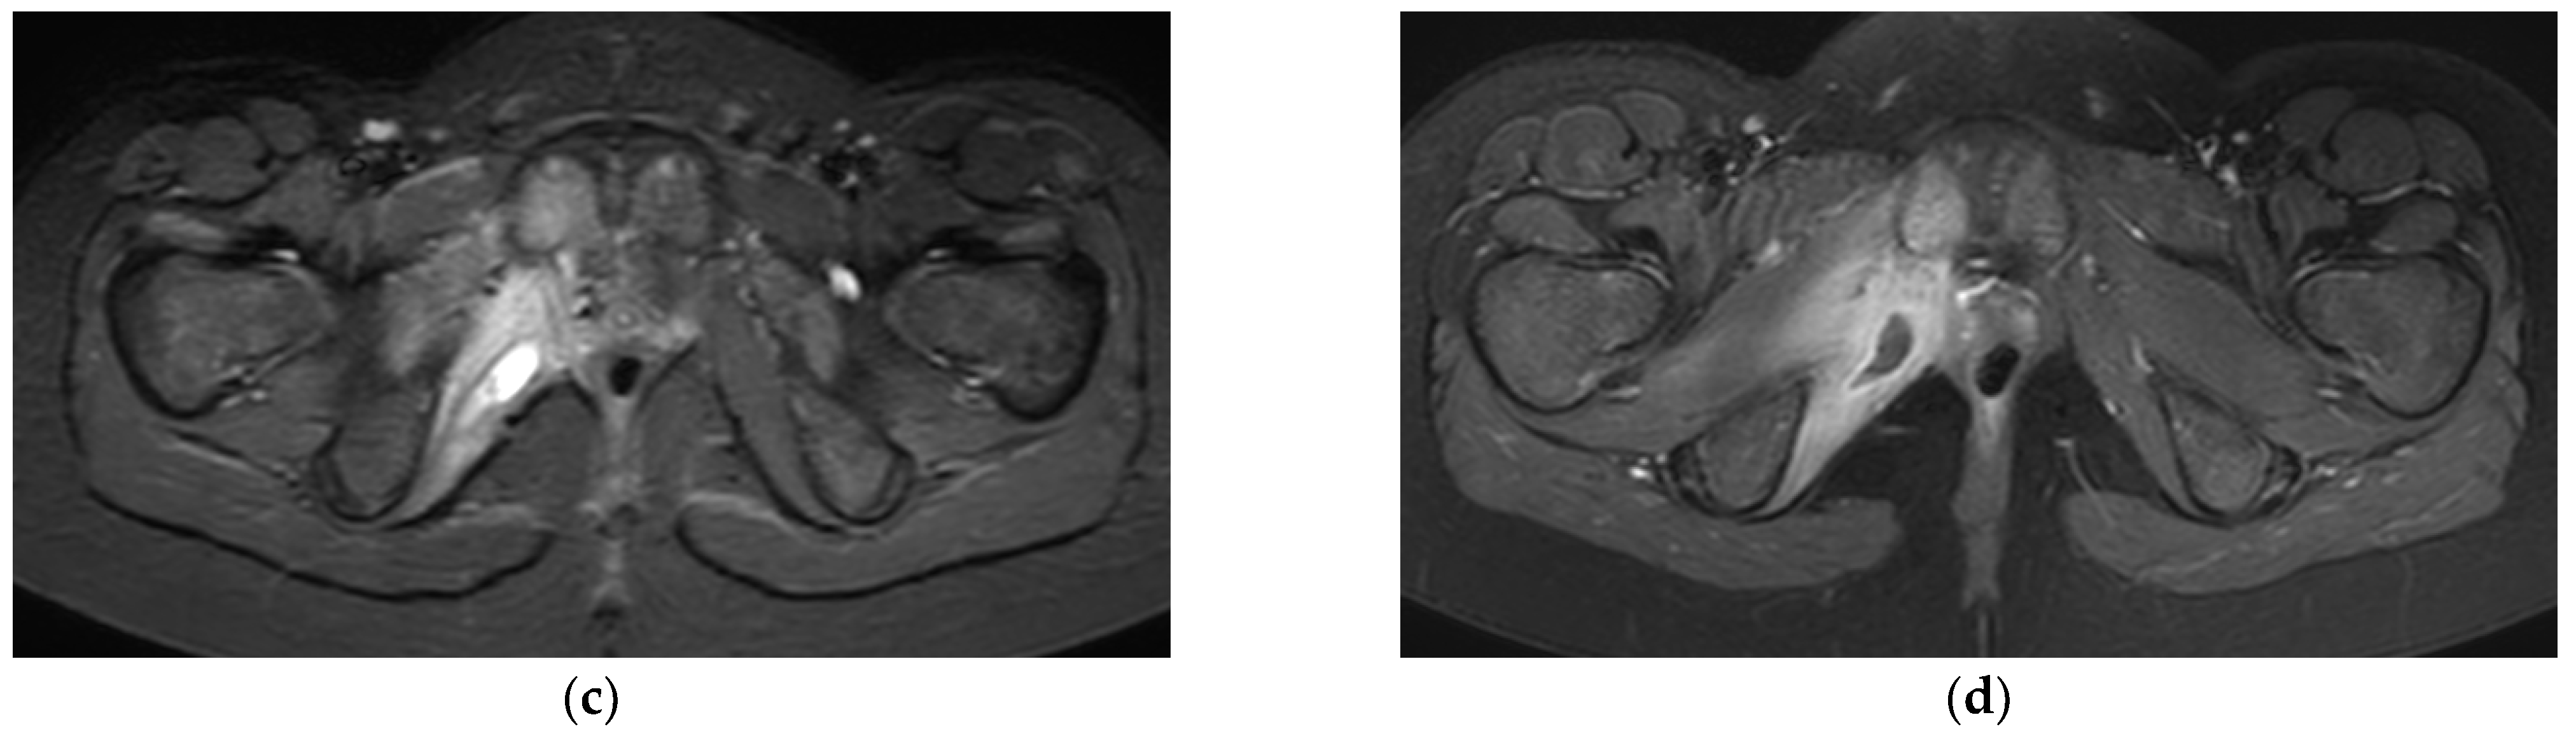

3.3. Radiologic Investigations